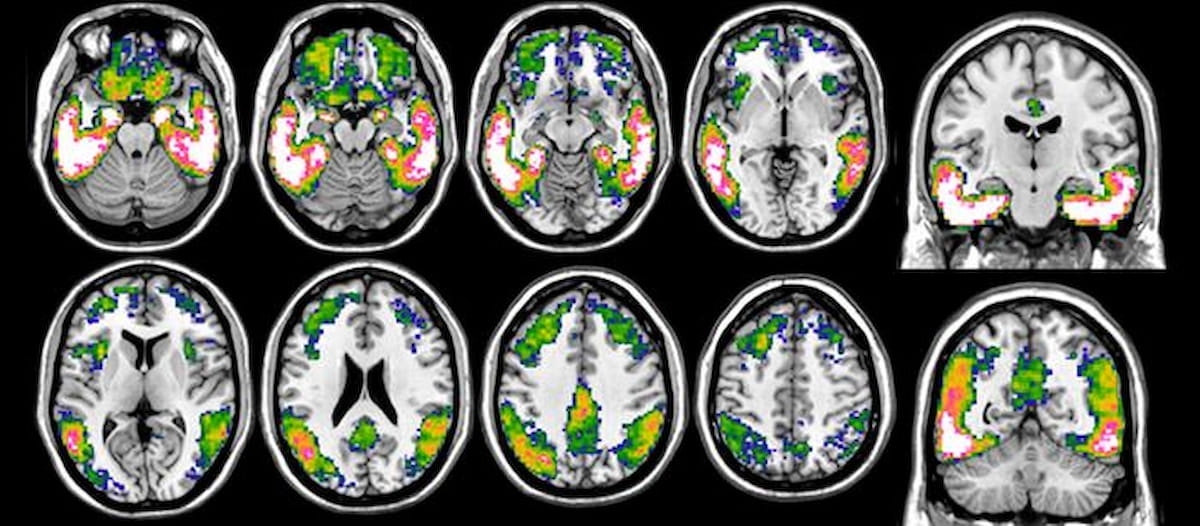

In the above tau-PET imaging, one can see more pronounced tau loads with the blue to white color scale and the highest accumulation in the pink-white areas. (Images courtesy of the University of Geneva.)

“Our voxel-wise results showed that decreased performance in global cognitive assessment was related to increased tau deposition and decreased metabolism (and brain volumes) in similar expected brain areas based on the well-known brain-behavior relationship,” wrote Valentina Garibotto, M.D., Ph.D., the head of the Nuclear Medicine and Molecular Imaging Division at University Hospital Centre Geneva in Geneva, Switzerland, and colleagues.